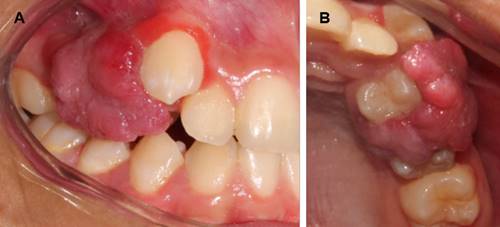

Al examen clínico intraoral de la consulta actual se evidenció una lesión de apariencia tumoral dolorosa a la palpación y a la masticación a nivel de encía marginal y alveolar de los dientes 1.4 y 1.5 (Fig. 1), de aproximadamente 3x3x3 cm de diámetro, que cubría las caras vestibular, palatina y parte de la corona clínica de dichos dientes. Su consistencia era firme, de aspecto lobulado y pediculado, y textura rugosa y sangrante ante el estímulo, con movilidad grado II del diente 1.4 (Fig. 2). Al examen radiográfico se observó borramiento de la cresta alveolar entre dientes 1.5 y 1.4 con mesioangulación y ensanchamiento del espacio periodontal del diente 1.4 (Fig. 3). En base a la evolución y características clínicas se planteó el diagnóstico presuntivo de granuloma piógeno o granuloma periférico de células gigantes.

Fig. 2 A: Vista frontal de la lesión cubriendo las caras vestibulares de los dientes 1.4 y 1.5. B: Vista oclusal de la lesión cubriendo las caras palatinas y parte de la corona clínica de los dientes 1.4 y 1.5